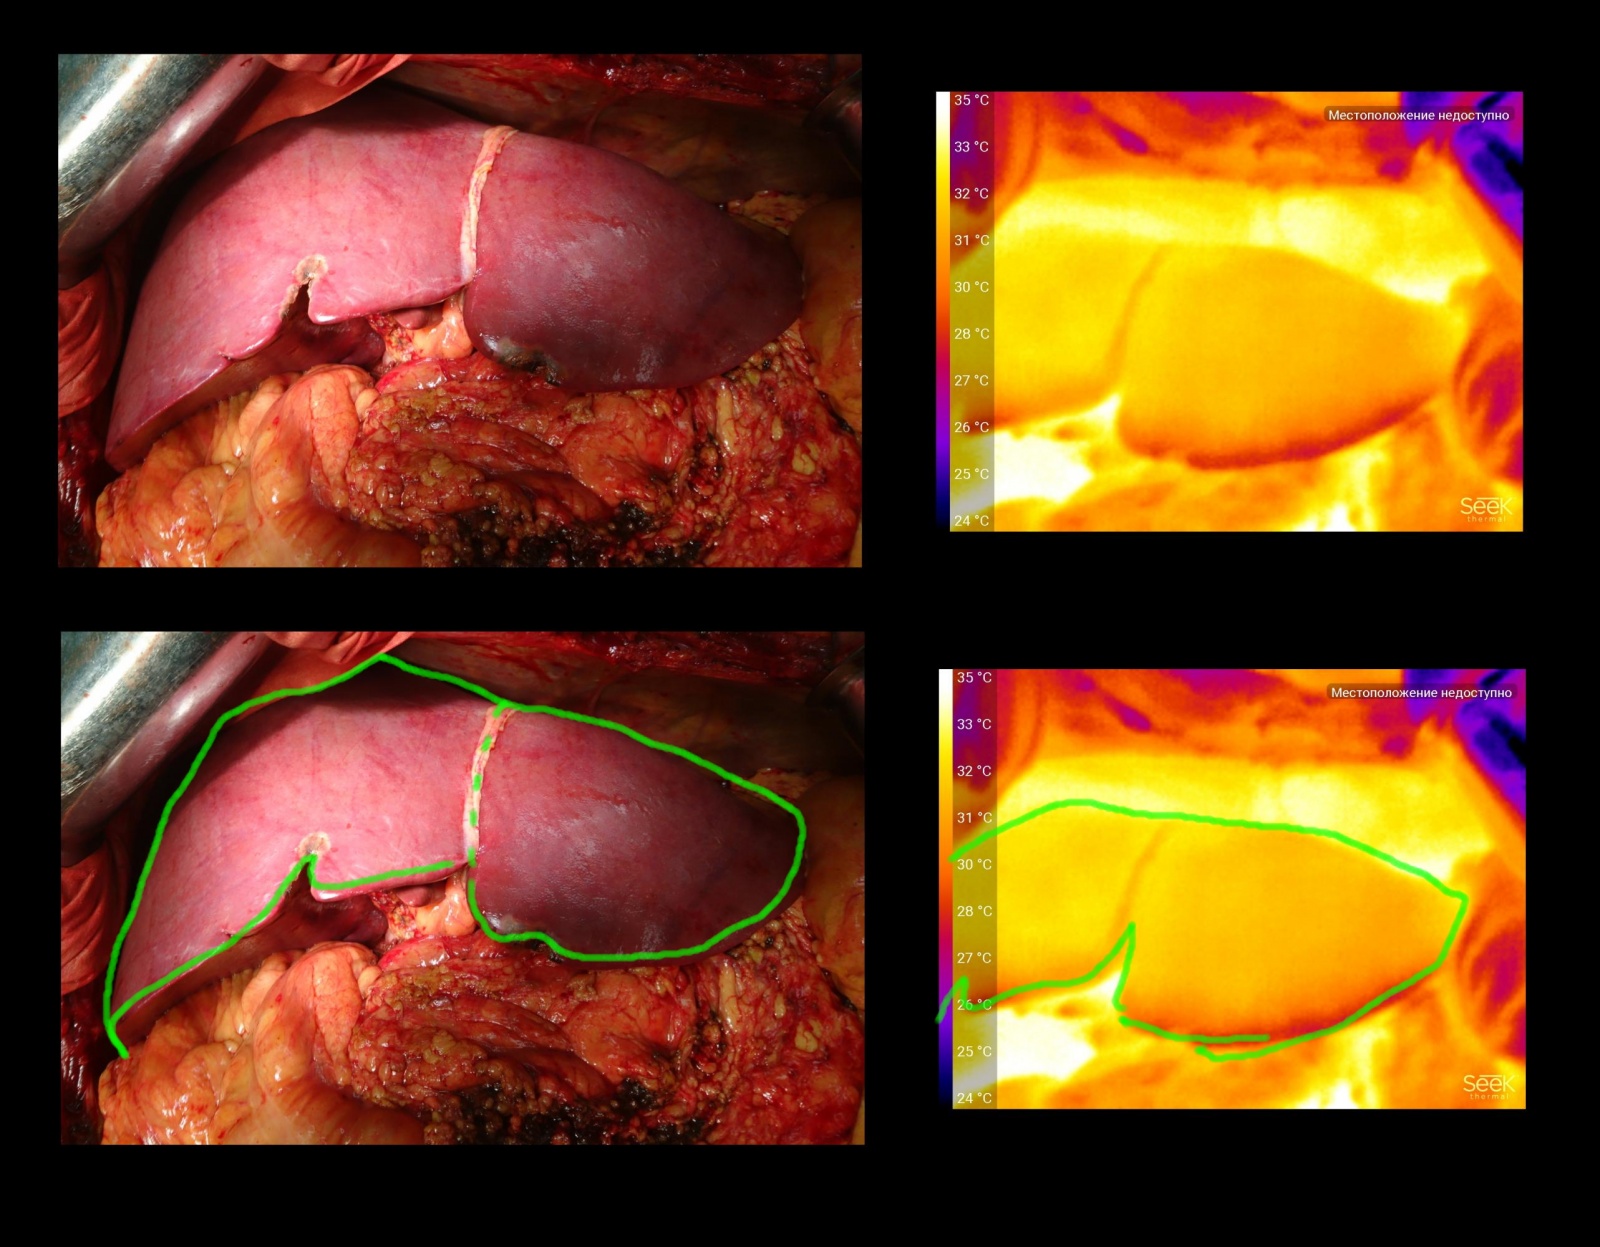

Трансплантат — половина печени. После пуска кровотока приобрёл правильную равномерно окраску.

На тепловизоре видно, что хуже всего кровоснабжаются ткани, расположенные под капсулой органа вдоль линии резекции, что вполне логично, так как при работе было термическое повреждение кровеносных капилляров и самой ткани. То, что правые сегменты выглядят сильно теплее — артефакт, они нагрелись от соседних органов. В данном случае, учитывая равномерность перехода цветов, можно сказать что перфузия адекватна.

Трансплантат — целая печень. Находилась на консервации несколько часов. Окраска также равномерна.

Трансплантат почки, снимок сделан сразу после пуска кровотока. Видно, что сначала восстанавливается температура в районе “ворот органа” — там, где впадают сосуды. На картинке это в нижней части почки. Синим отмечены несколько фрагментов околопочечного жира — он не кровоснабжается от почечных сосудов, поэтому остаётся более холодным.

Иногда, чтобы вызвать рефлекторное расслабление сосудистых стенок, трансплантат легко массируют. На видео видно, как после этого температура всей поверхности поднялась (ткани немного нагрелись от руки), но потом сама почка эту температуру сохранила за счет улучшения кровотока, а фрагмент жира остыл до изначального состояния.